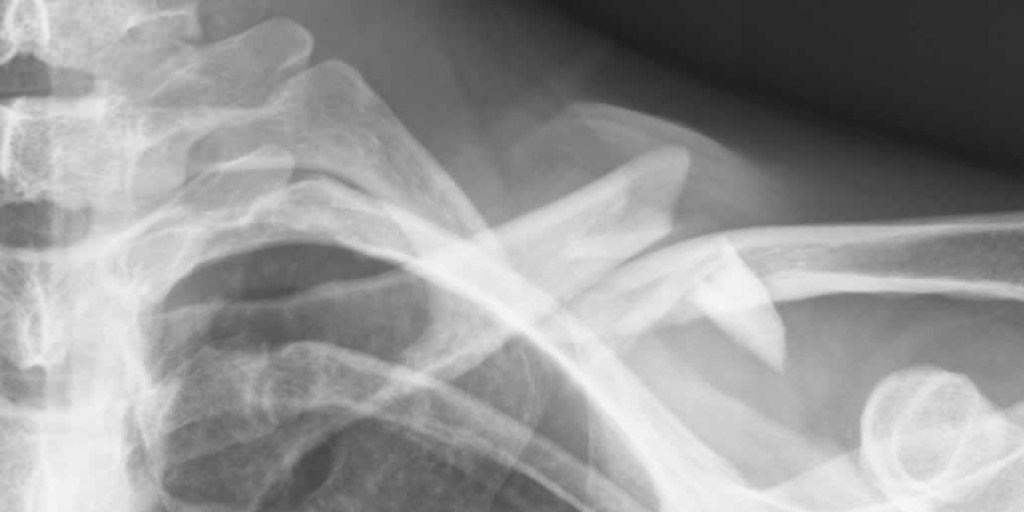

Radiologists from other hospitals have been tasked with reading medical images taken at the LMH – such as x-rays – while SA Health fills vacancies.

Image: Matt Clare